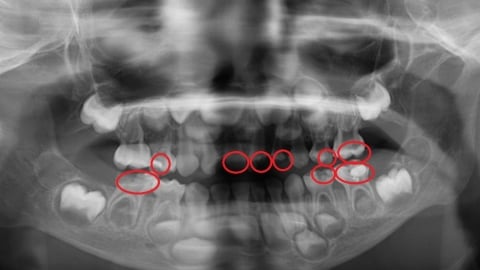

▲人工顳顎關節